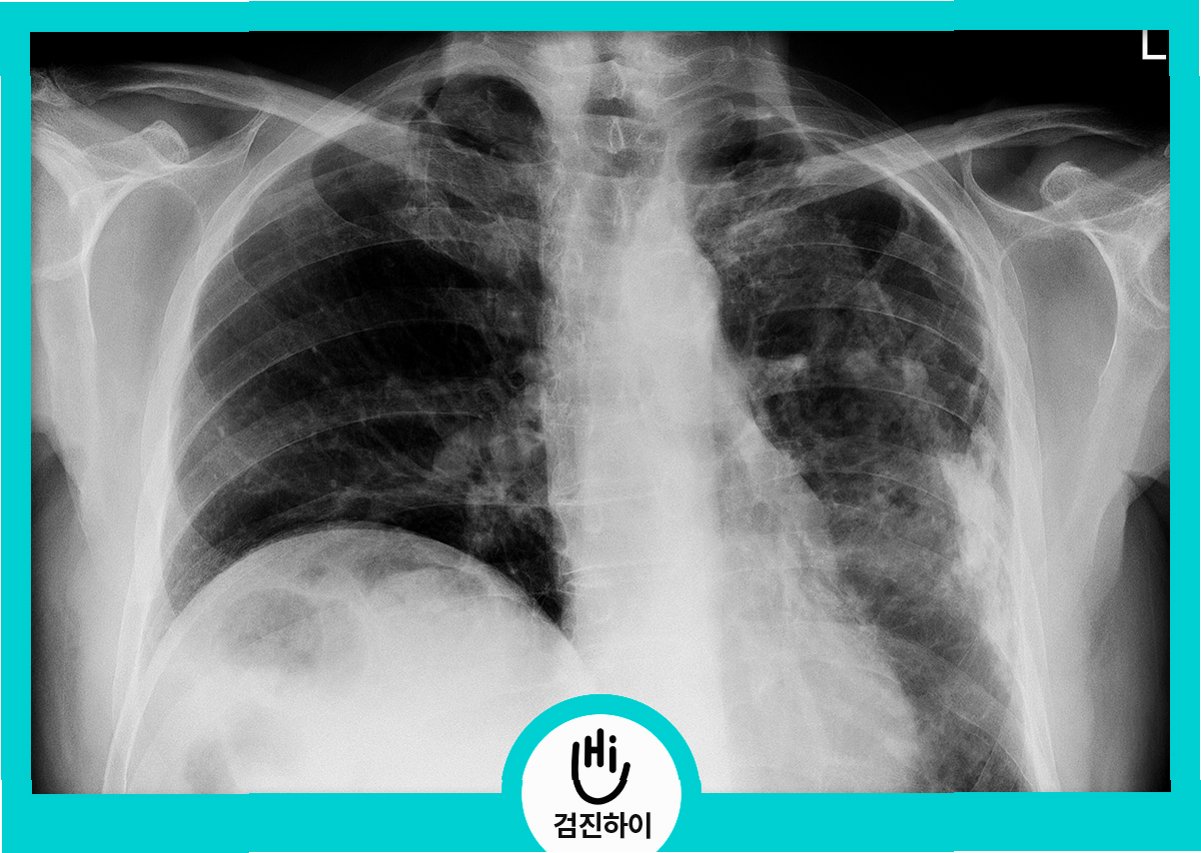

결핵 검사는 크게 흉부 X-ray 촬영, 객담 검사, 결핵균 검사(배양 검사), 결핵 피부 반응 검사(투베르쿨린 검사) 및 혈액 검사(IGRA) 등으로 이루어집니다. 흉부 X-ray는 폐의 결핵 병변을 확인하는 데 사용되며, 객담 검사는 가래에서 결핵균을 찾아내는 검사입니다. 결핵균 검사는 결핵균의 존재 여부를 확인하는 가장 정확한 방법 중 하나입니다. 결핵 피부 반응 검사는 결핵균에 대한 면역 반응을 확인하는 검사이며, 혈액 검사는 결핵균 감염 여부를 확인하는 데 사용됩니다. 검사 방법은 환자의 상태와 의심되는 부위에 따라 결정되며, 의료진의 판단에 따라 필요한 검사가 진행됩니다. 검사 결과에 따라 추가 검사가 필요할 수도 있습니다.